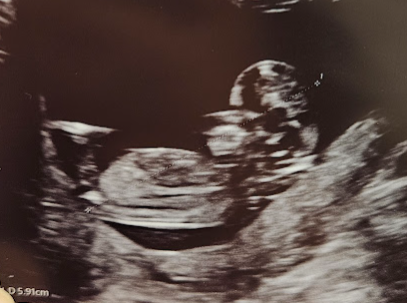

임신 기록이 몇주 밀려서 한번에 요약해보는 7~9주의 3주간의 임신 초기 기록 * 7주 ~ 9주 : 2023/12/26 ~ ...